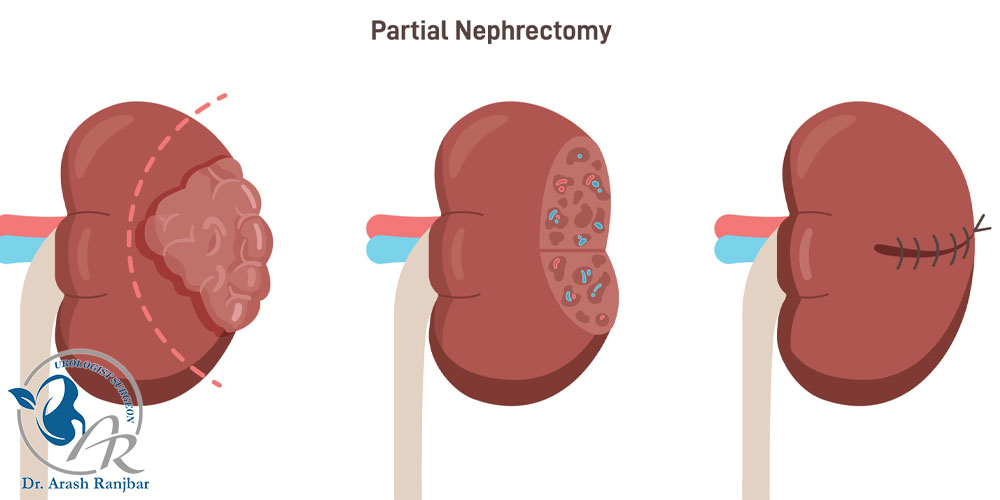

۱. نفرکتومی جزئی: در این شیوه، تنها قسمتی از بافت کلیه که دچار تومور یا آسیب شده برداشته می شود. این روش برای افرادی که توده های کوچک دارند یا حفظ بافت کلیه برایشان ضروری است، انتخاب مناسبی محسوب می شود.